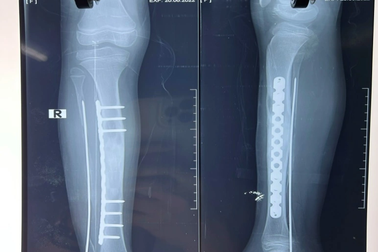

Bị đau chân, bé gái 10 tuổi phát hiện u xương chày dài 12cmKhi con gái 10 tuổi kêu đau chân, gia đình nghĩ đơn giản do bé vận động nhiều. Kết quả chẩn đoán cho thấy bệnh nhi bị loạn sản xơ xương cẳng chân phải, được phẫu thuật lấy khối u xương chày dài 12cm.